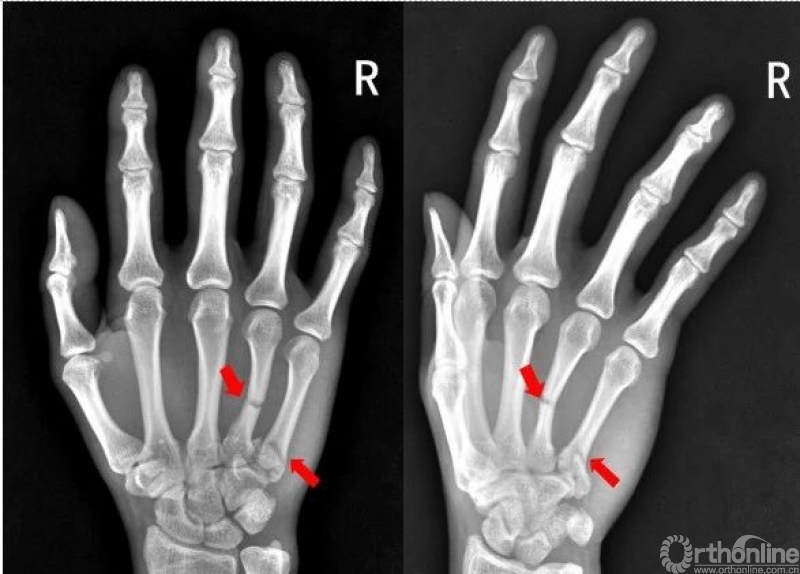

右手第五掌骨远端骨皮质不连续,骨折端移位、成角。右手第五掌骨骨折(1-5. 第1-5掌骨)

右手第四掌骨中段、第五掌骨基底部见横行骨折透亮线,骨折端对位对线尚可。第四、第五掌骨骨折